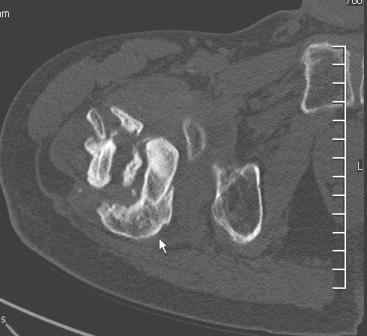

Сросшийся со смещением чрез-подвертельный перелом

Больной Н. 44 года травма 1,5 года назад июнь 2008 года чрез-под вертельный перелом правого бедра. Во время лечения у больного развился алк. делирий, проводилось консервативное лечение перелома.

Беспокоят боли, укорочение конечности. Укорочение 3 см. Ногу поднимает, сгибание ограничено, ротационные движения в полном объеме. На КТ перелом сросся за счет костной мозоли. Что делать?

Протез? Если «да» Можно ли обойтись стандартной ножкой Corail?

Или межвертельная остеотомия?